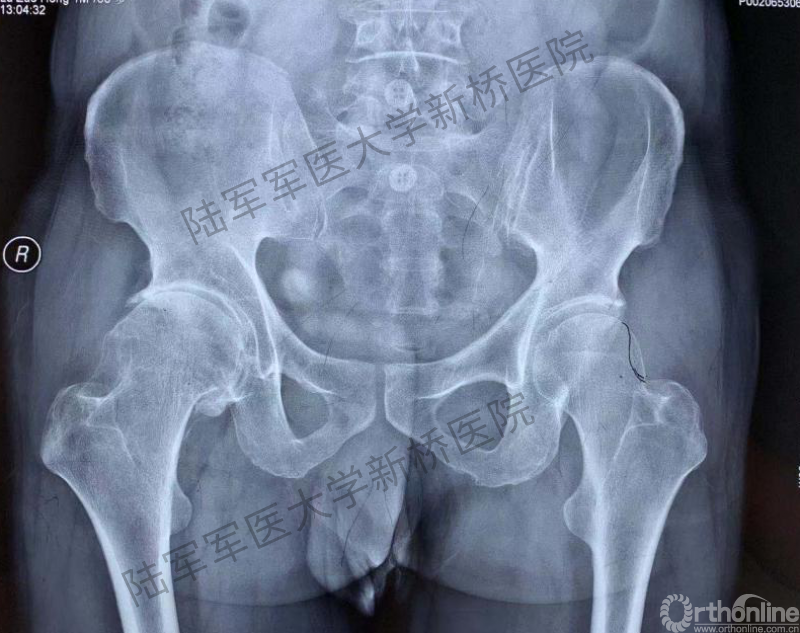

患者术前骨盆前后位X线片

对患者骨盆正位、特别是双侧髋关节局部特征进行观察,此例手术存在较多的骨性和软组织性陷阱。其一,患者为冠状面的双侧髋外翻畸形,双侧CCD角度高达148°,远远超出正常髋关节的生理范围。目前常规股骨假体最大的CCD角也仅有137°,个体化髋关节重建难度高。其二,右侧髋关节因骨性撞击导致股骨头粗大(左侧股骨头直径46mm,右侧股骨头直径54mm),由此导致髋关节周围关节囊360°膨胀性拉长,由此导致髋关节静态稳定结构松弛,术后脱位风险增加!其三,髋臼硬化、形变严重,术中髋臼解剖旋转中心处打磨容易出现偏差。其四,最棘手的是由于撞击导致外展肌过度延长,最终结果是右侧的髋臼偏心距和股骨偏心距均显著外移,由此带来髋关节动态稳定肌群的松弛和菲薄,术后脱位风险进一步增加!在如上困境中,选择常规假体进行手术,往往出现两个极端:要么下肢延长,要么关节脱位。常规术前计划系统,如等比例胶片法、或基于二维X线的计算机软件测量系统,均难以在两者间实现平衡。而基于人工智能深度学习技术与手术模拟算法、图像算法结合,依靠计算机辅助的方式来实现关节置换手术的三维术前规划--AI HIP系统,是解决上述问题的理想选择。